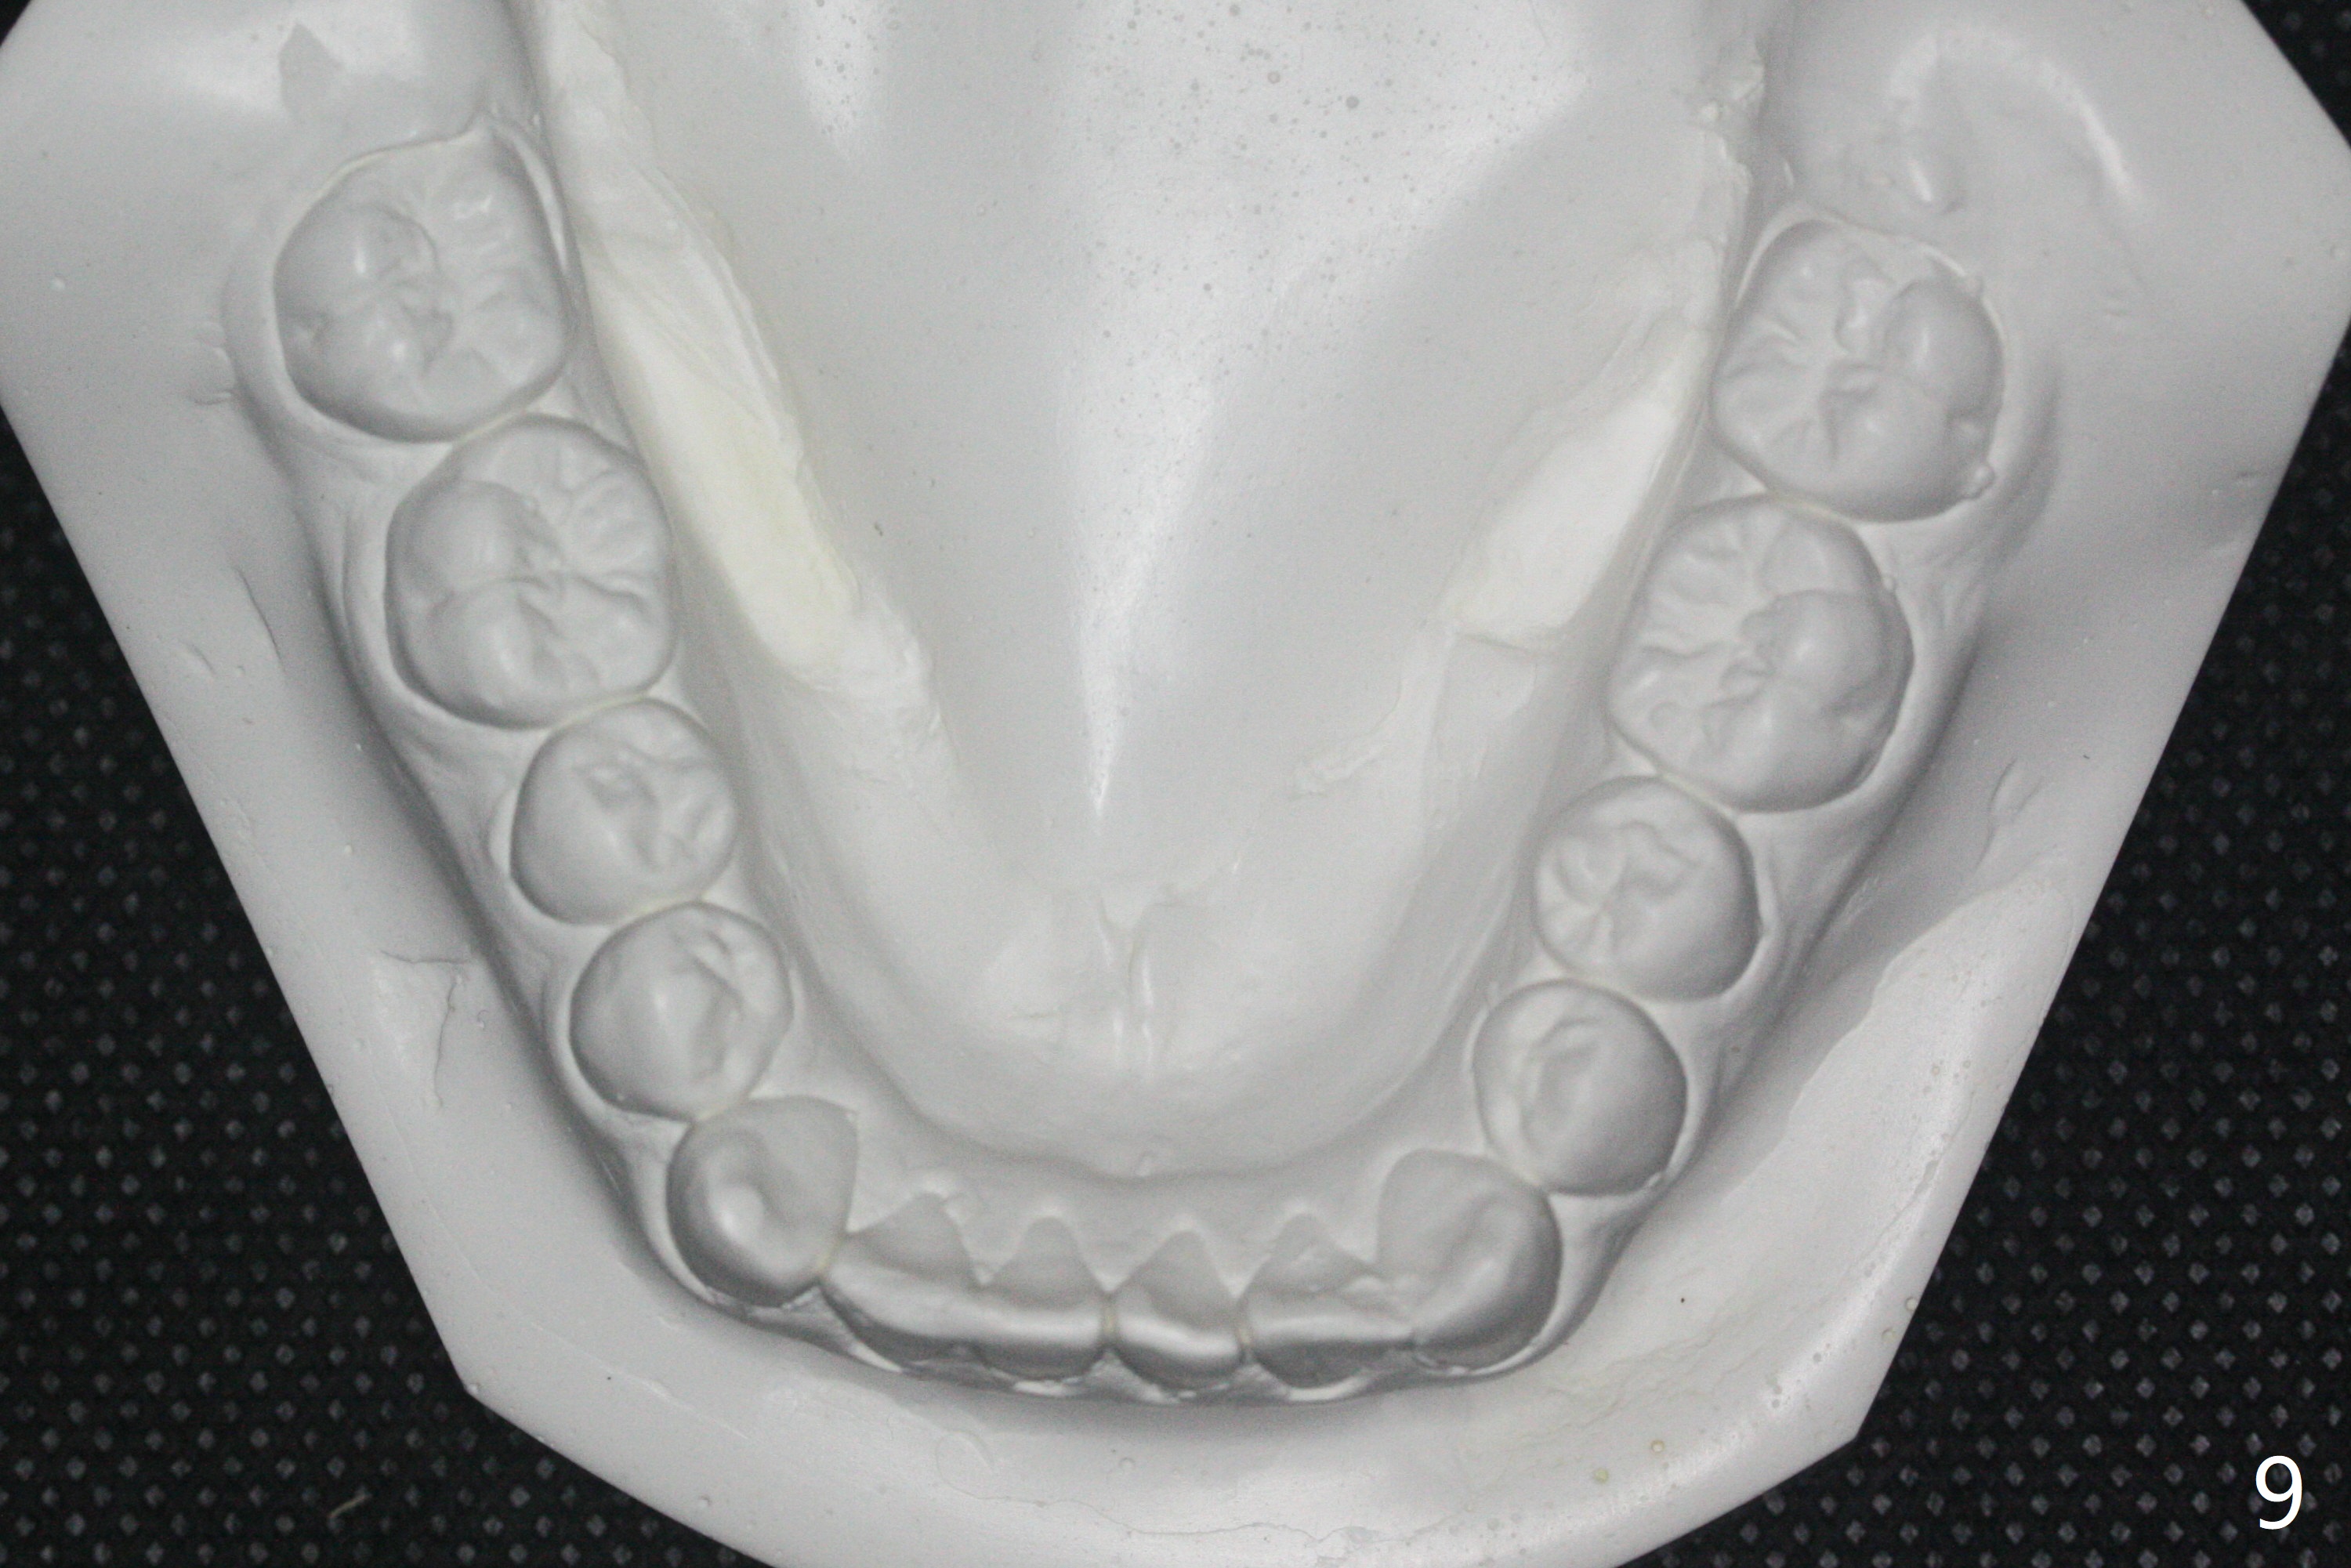

15岁男完成矫正1年9月,右侧后牙咬合理想(图二),上中切牙长轴改善,侧切牙torque不够完善(图四),左侧后牙咬合二类𬌗(图六,需要牵引),磨牙缝隙大(图八,十),造成食物堵塞,以后尽量避免使用磨牙bands,尤其是成人。